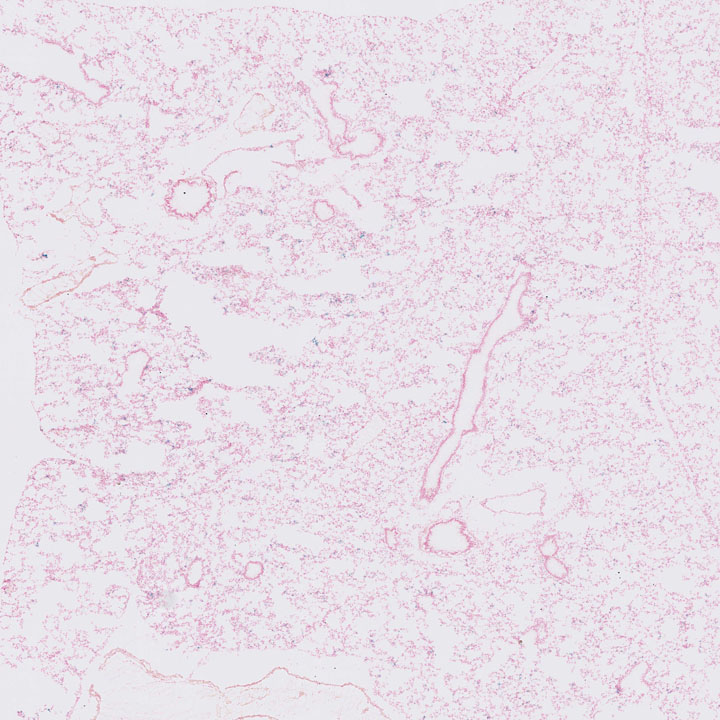

Fig. Lepr P56 Lung

J:193672

Fig. Lepr P7 Lung